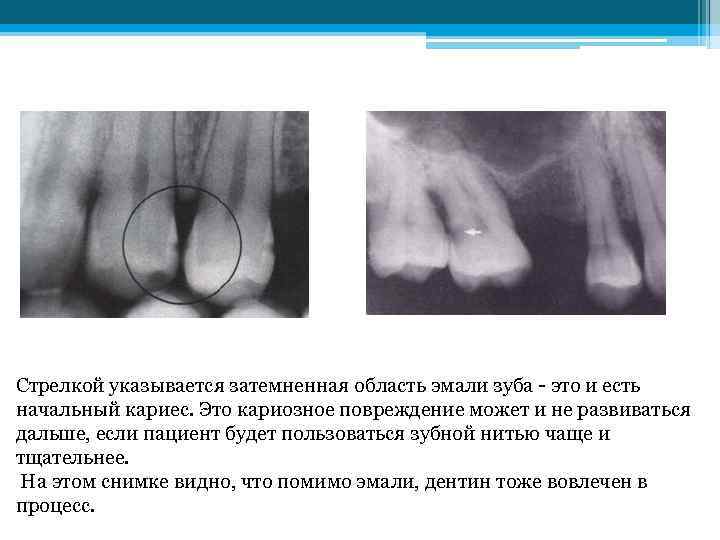

Твердые минерализированные ткани зуба не пропускают рентгеновские лучи, проходящие сквозь зубы на рентгеновской пленке. Поэтому на те участки пленки, которые были закрыты эмалью и дентином зуба, попадало меньше рентгеновских лучей, а на снимке эти участки выглядят более светлыми. Поскольку в областях кариеса минералы твердых тканей разрушены, эти области будут выглядеть затемненными. Это происходит по той причине, что кариозная область становиться менее твердой или разрушенной, и значит, через нее могут проходить рентгеновские лучи и попадать на рентгеновскую пленку. Для полного понимания всего этого, рассмотрим рентгеновские снимки. На этом снимке мы можем увидеть самую раннюю стадию образования кариеса, которую может уловить рентгеновский снимок.

Твердые минерализированные ткани зуба не пропускают рентгеновские лучи, проходящие сквозь зубы на рентгеновской пленке. Поэтому на те участки пленки, которые были закрыты эмалью и дентином зуба, попадало меньше рентгеновских лучей, а на снимке эти участки выглядят более светлыми. Поскольку в областях кариеса минералы твердых тканей разрушены, эти области будут выглядеть затемненными. Это происходит по той причине, что кариозная область становиться менее твердой или разрушенной, и значит, через нее могут проходить рентгеновские лучи и попадать на рентгеновскую пленку. Для полного понимания всего этого, рассмотрим рентгеновские снимки. На этом снимке мы можем увидеть самую раннюю стадию образования кариеса, которую может уловить рентгеновский снимок.

Стрелкой указывается затемненная область эмали зуба - это и есть начальный кариес. Это кариозное повреждение может и не развиваться дальше, если пациент будет пользоваться зубной нитью чаще и тщательнее. На этом снимке видно, что помимо эмали, дентин тоже вовлечен в процесс.

Стрелкой указывается затемненная область эмали зуба - это и есть начальный кариес. Это кариозное повреждение может и не развиваться дальше, если пациент будет пользоваться зубной нитью чаще и тщательнее. На этом снимке видно, что помимо эмали, дентин тоже вовлечен в процесс.